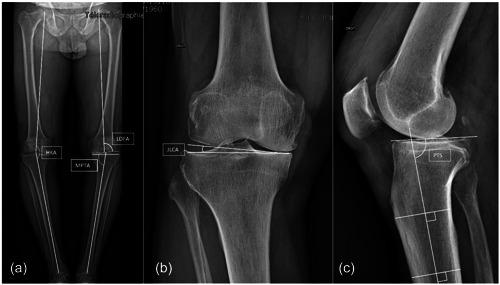

A retrospective analysis of prospective collected data was performed. Between March 2011 and May 2018, 49 patients with isolated medial knee osteoarthritis who were operated for OWHTO using PSCG and 38 patients using the standard technique were included. Preoperative and postoperative deformities were evaluated on long leg radiographs by measuring the mechanical medial proximal tibial angle, mechanical lateral distal femoral angle, hip knee ankle angle (HKA), and joint line convergence angle. Pre- and postoperative posterior tibial slope was also evaluated. Accuracy was evaluated by analysing the difference between the preoperative planned and the actual postoperative HKA. Operating time and complication rate were also recorded in both groups.

对前瞻性收集的数据进行回顾性分析。纳入2011年3月至2018年5月期间因OWHTO接受手术的49例孤立性内侧膝关节骨关节炎患者,其中49例使用PSCG,38例使用标准技术。通过测量机械性胫骨近端内侧角、机械性股骨远端外侧角、髋膝踝角(HKA)和关节线汇聚角,在长腿X线片上评估术前和术后畸形情况。还评估了术前和术后的胫骨后倾。通过分析术前计划的和实际术后HKA之间的差异来评估准确性。记录两组的手术时间和并发症发生率。